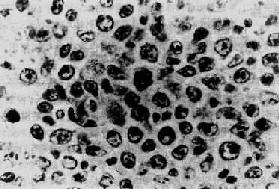

���⣬����һ���ܰ���Ҳ��Դ��С����ϸ������������Burkitt�ܰ������Ƶ�ϸ����ǣ�������֯�ṹ�Ͳ��˵�Ԥ����Burkitt�ܰ�����ͬ����Ϊ��Burkitt�ܰ�������Burkitt�ܰ�������ϸ���Ƚ϶����ԣ���С��һ��ϸ���˴�СҲ��һ�¡����ʴ�����ԣ���ʱֻ��һ������ʡ�����ϸ����ɵġ������ǡ��������ͼ11-5������Burkitt�ܰ����Ƚ��ټ�������ڳ����ˣ�����Ч���ϲԤ��Ҳ�ϲ

ͼ11-5 С������������ϸ�����ܰ�������Burkitt�ܰ���

��ϸ������һ�£������٣��˶�ΪԲ�Σ���С��״Ҳ��һ��